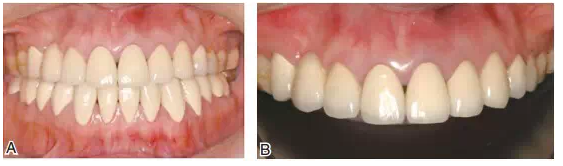

圖19患者修復完成后的正面像及牙合曲線